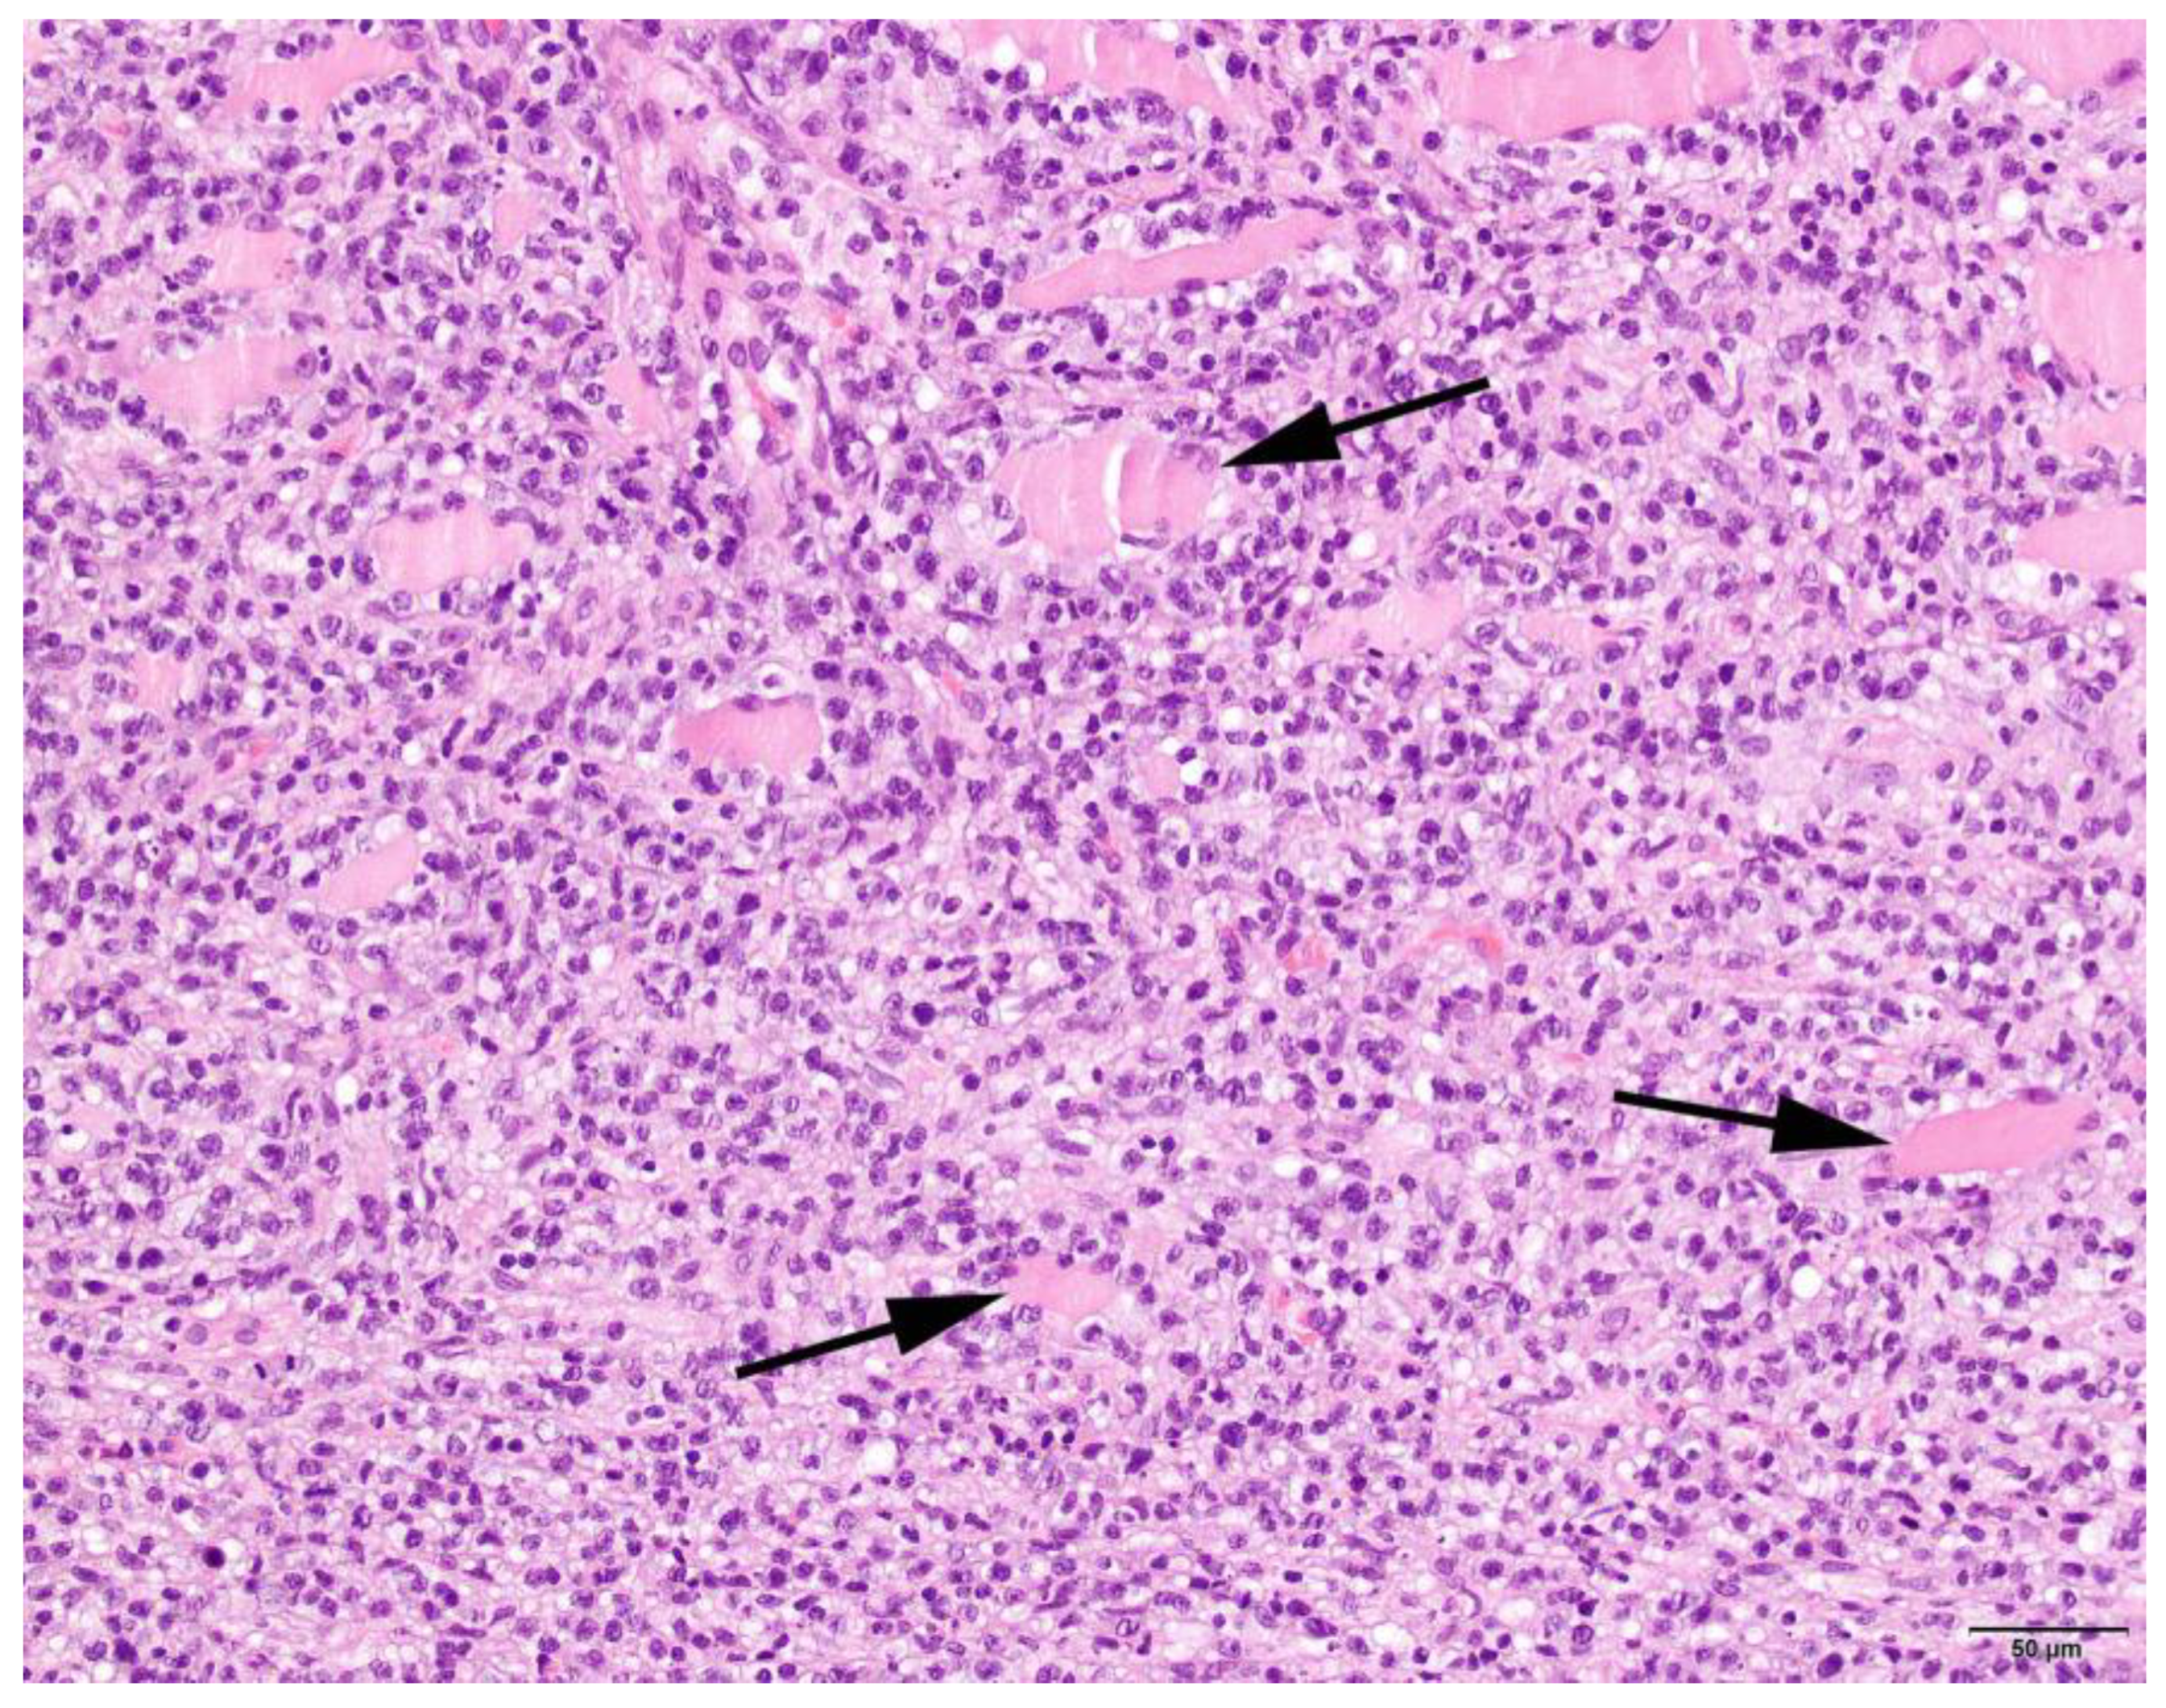

3.4. Histopathology

| Pattern | Expanse | Phase | Location Infiltrate | ||||||

|---|---|---|---|---|---|---|---|---|---|

| Focal | 2 | Mild | 5 | Subacute | 4 | Degeneration | 63 | Endomysium | 27 |

| Multifocal | 63 | Moderate | 13 | Chronic | 29 | Regeneration | 38 | Endomysium and perimysium | 17 |

| Severe | 9 | Atrophic | 25 | Perimysium | 5 | ||||

| Necrosis | 31 | ||||||||

| Fibrosis | 35 | ||||||||

| Characterization of Infiltrate and Severity | |||||||||

|---|---|---|---|---|---|---|---|---|---|

| Lymphocytes | Neutrophils | Eosinophils | Histiocytes | Plasmacells | |||||

| + | 18 | + | 25 | + | 22 | + | 16 | + | 22 |

| ++ | 29 | ++ | 10 | ++ | 8 | ++ | 28 | ++ | 14 |

| +++ | 22 | +++ | 4 | +++ | 6 | +++ | 31 | +++ | 5 |